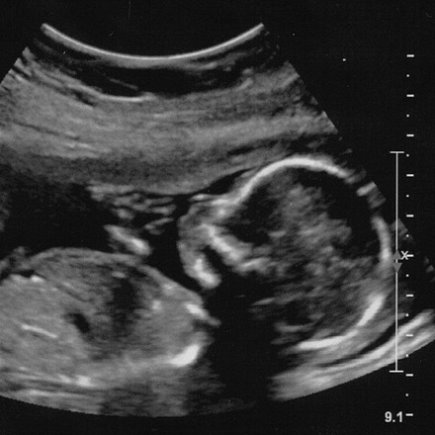

Two recent breakthroughs by Great Ormond Street Hospital and University College London will make it significantly easier for an unborn baby’s DNA to be tested by sampling the mother’s blood.

It’s long been shown that testing an unborn baby’s DNA – also known as ‘prenatal DNA testing’ – is beneficial. Screening for congenital disorders is one of the most obvious benefits, with gender and paternity testing also being valuable to the right parent. In addition, new tests will soon show an unborn baby’s genetic intolerance to various medications, easing our ability to deal with difficult pregnancies.

Unfortunately, there have been a few major problems with trying to take an unborn baby’s DNA sample. The first is that looking for the baby’s DNA in the mother’s blood – known as non-invasive testing – has been difficult, the second is that trying to test the baby’s DNA directly – known as invasive testing – has a 1-2% chance of triggering spontaneous miscarriage.